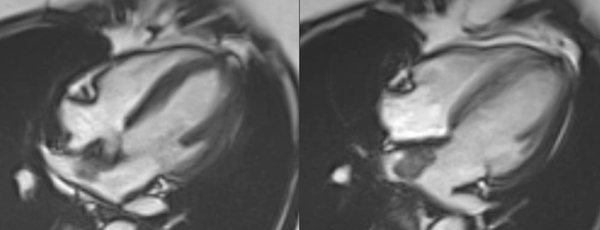

Tumors Snippet 212: Real Masses - Diagnosable A snippet on tumors that in most instances can be readily diagnosed.